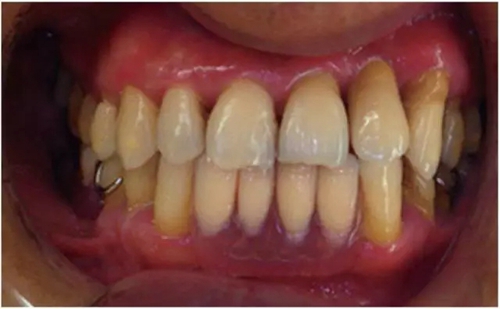

戴種植義齒(圖9~12)。

圖12 戴義齒口內(nèi)照片